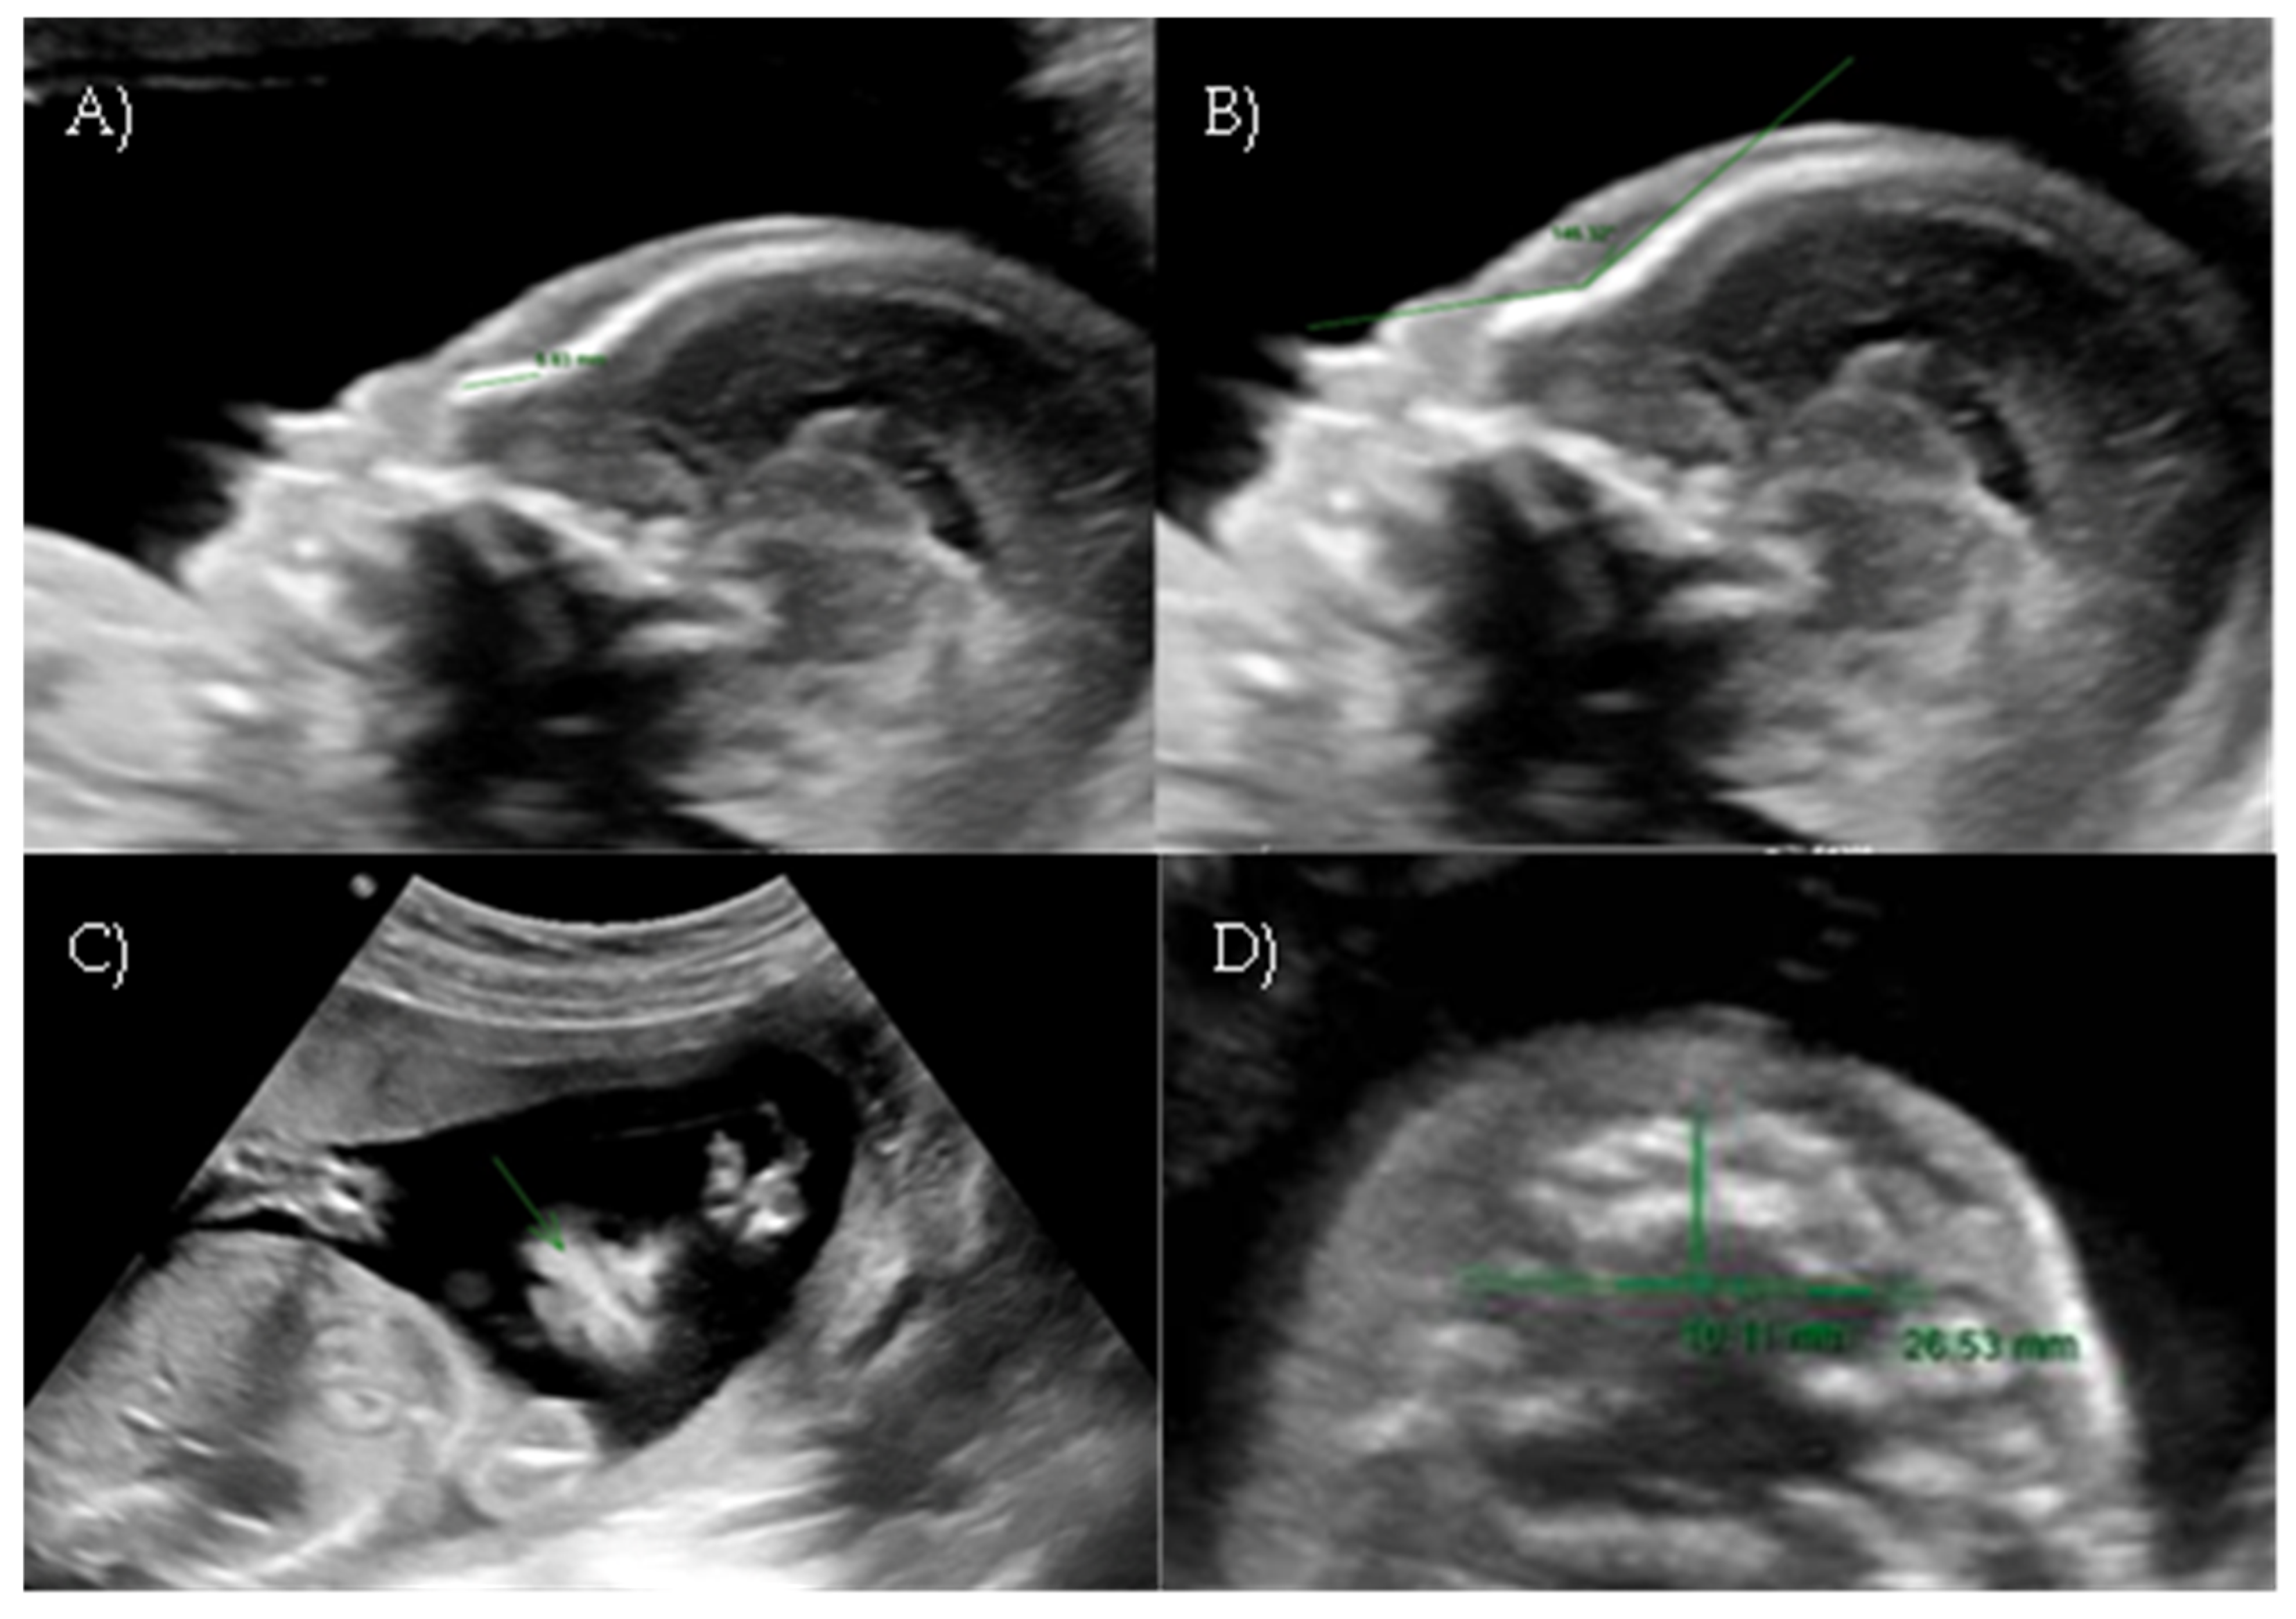

A targeted anomaly scan at our fetal medicine unit revealed a flat and dysmorphic fetal facial profile with verticalization of the nasal bone, increased NFA, and short columella, suggestive of BP. An associated feature was polyhydramnios. The ultrasound findings were suggestive of Binder-type maxillonasal dysplasia (Nasal-frontal angle: 146.32°, cut-off: <143°) such as the flattening of the curvature of the maxillary alveolar processes (Width: 26.53 mm, cut-off at 22 weeks: 23.9 mm) (Figure 6A–D).

Figure 6. Case 6. (A) Flat fetal profile with verticalization of the nasal bone. (B) Nasal-frontal angle: 146.32°. (C) Absent nasolabial philtrum. (D) Flattening of the curvature of the maxillary alveolar processes. Width: 26.53 mm.